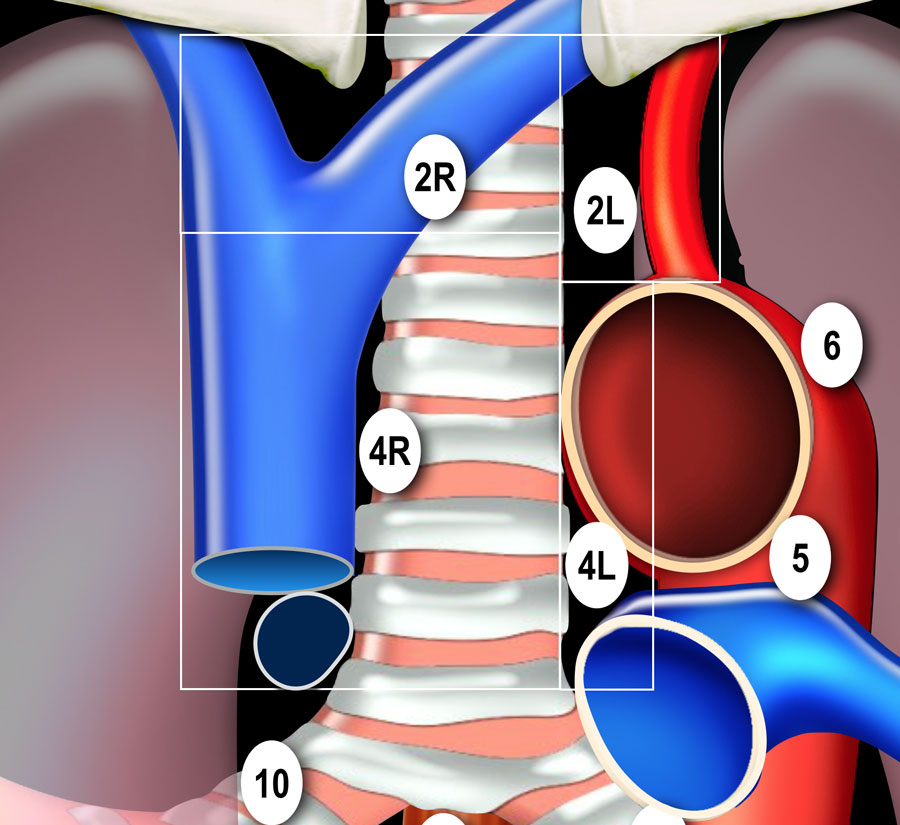

N-стадирование Классификация регионарных лимфатических узлов IASLC 2009 г.

Граница между лимфатическими узлами 10 и 4 группы находится на правой нижней границе непарной вены и на левой верхней границе легочной артерии (отличие N1 и N2 стадий). Достаточно важно разделять лимфатические узлы 1-ой группы и 2/3-ей групп

(отличие N3 и N2 стадий). Граница между группами лимфатических 4R и 4L является левый латеральный контур трахеи, а не срединная линия. Паракардиальные, лимфатические узлы молочных желез, диафрагмальные,

межреберные и подмышечные лимфатические узлы не входят в карту

лимфатических узлов согласно IALSC, несмотря на то, что они редко, но

могут вовлекаться в патологический процесс. ПЭТ/КТ является методом выбора при определении N-статуса. |